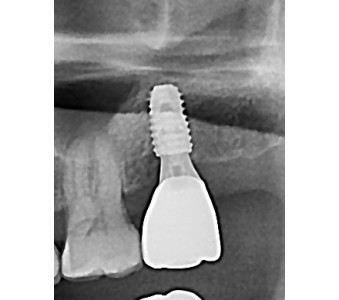

오스템 임플란트 프리미엄 BA 등급 사용

같은 오스템이라도 등급이 다릅니다. 더 빠른 골유착을 위해 프리미엄 등급을 사용합니다.

결과로 증명합니다.

국제모아치과의

실제 임상 증례